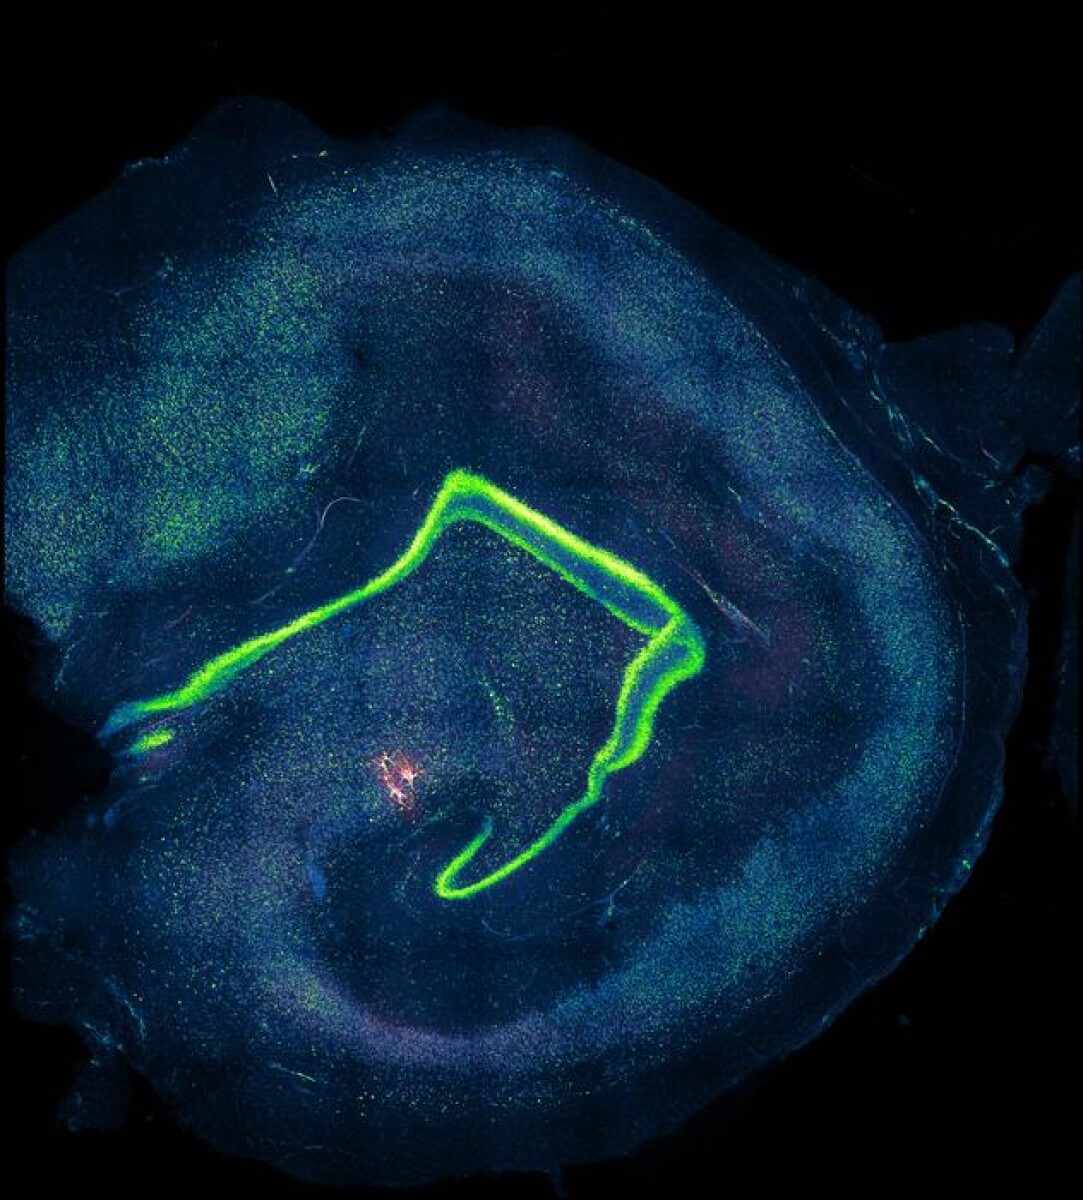

Human CA3 pyramidal neurons recorded in a patient tissue sample. (Credit: © Jake Watson)

Using cutting-edge techniques like multicellular patch-clamp recording and super-resolution microscopy, the researchers discovered that the human brain’s neural connectivity is fundamentally different from what we’ve observed in mice. The human hippocampus, specifically a region called CA3 crucial for memory storage, has sparser connections between neurons. Surprisingly, these connections are also more reliable and precise.

The researchers studied how human hippocampal CA3 neurons work by analyzing brain tissue from epilepsy surgery patients. They used advanced techniques like multicellular patch-clamp recording and superresolution microscopy to observe the structure and connections of neurons in this region. The team also developed computational models to understand how these networks store memories. They focused on “non-sclerotic” tissue, ensuring they studied healthy-like samples. These experiments revealed how the CA3 circuit connects sparsely but reliably to enhance memory capacity.

The study found that the human CA3 region in the brain, crucial for memory, has a unique way of working. Unlike other parts of the brain, CA3 uses sparse but precise connections, meaning fewer neurons connect with each other, but they do so reliably. This setup allows the brain to store and recall memories efficiently without overload. The findings also showed that human CA3 neurons have extended dendrites (branches) and longer-lasting signals compared to rodents, giving humans a more powerful memory network.